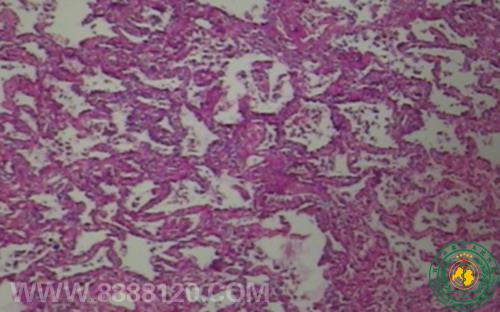

我科推出低剂量螺旋CT技样与肺癌早期筛查

我科推出低剂量螺旋CT技样与肺癌早期筛查10483